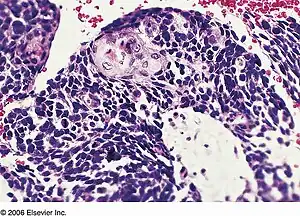

| Combined small cell lung carcinoma containing a component of squamous cell carcinoma | |

Combined small cell lung carcinoma (or c-SCLC, and rarely rendered as "small-cell lung carcinoma") is a form of multiphasic lung cancer that is diagnosed by a pathologist when a malignant tumor arising from transformed cells originating in lung tissue contains a component of small cell lung carcinoma (SCLC) admixed with one (or more) components of non-small cell lung carcinoma (NSCLC).[1][2][3]